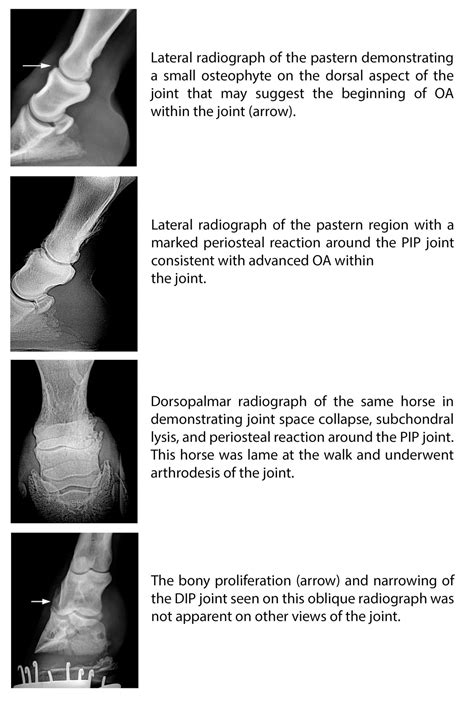

Ring bone in horses is a degenerative joint disease that affects the pastern joint or the coffin joint. It is characterized by the formation of bony growths around the joint, which can lead to stiffness, lameness, and reduced mobility. The condition is often classified into two types: high ringbone and low ringbone.

High ringbone affects the pastern joint, which is located higher up on the leg. This type of ringbone is less common but can be equally debilitating. It often results from trauma or repetitive stress on the joint, leading to the formation of bony spurs and inflammation.

Low ringbone, on the other hand, affects the coffin joint, which is closer to the hoof. This type is more common and is often associated with poor conformation, overuse, or injury. The bony growths in this area can cause significant discomfort and lameness, making it difficult for the horse to move comfortably.

• Imaging: Radiographs (X-rays) are often used to visualize the bony growths and assess the extent of the damage. In some cases, ultrasound or MRI may be recommended for a more detailed view.